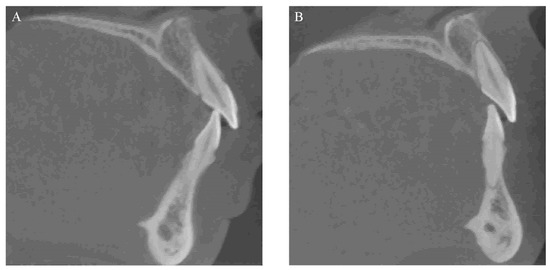

Figure 6 shows a representative example of alveolar bone resorption in both maxillary and mandibular central incisors after orthodontic treatment.

Figure 6. A representative example of alveolar bone resorption in both maxillary and mandibular central incisors after orthodontic treatment: (A) alveolar bone status before orthodontic treatment; (B) absorbed alveolar bone after orthodontic treatment.